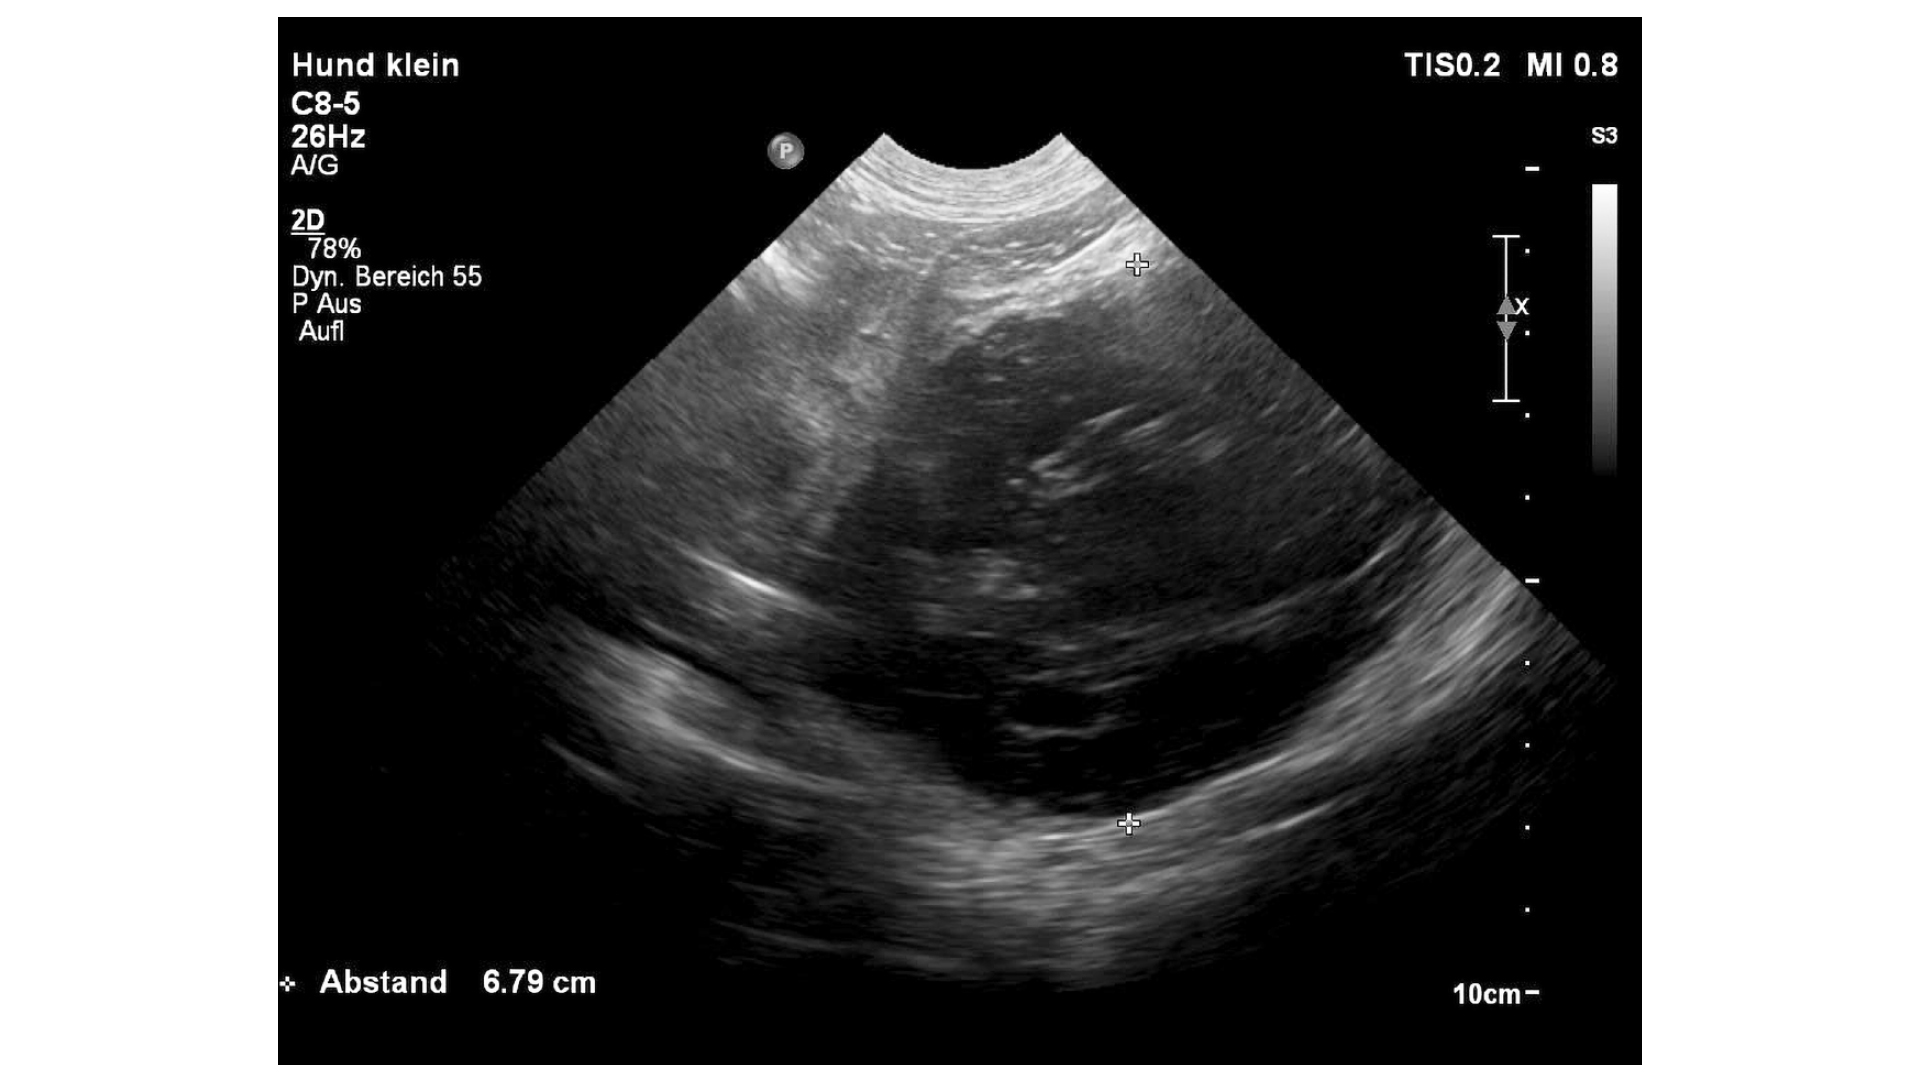

Bei der Blutchemie waren alle untersuchten -Organwerte in der Norm. Das Blutbild zeigte einen normalen Hämato-krit (42 Prozent), eine Thrombozytopenie (69 K/µL), eine Retikulozytose (137 K/µL) und eine Leukozytose (27 K/µL) mit Neutrophilie und Monozytose. Das C-reaktive Protein (CRP) war mit 162 mg/l (0–10) deutlich erhöht. Die Thrombozyten von Akiro wurden bereits bei vorhergehenden Untersuchungen mittels Blutausstrich kontrolliert und als Megathrombozyten und demnach als nicht pathologisch diagnostiziert. Die Röntgenuntersuchung des Thoraxes in zwei Ebenen erschien unauffällig (Abb. 1), wohingegen der Ultraschallbefund deutliche Veränderungen zeigte. Neben einem mittelgradigen Aszites war im kaudalen Abdomen eine circa sechs Zentimeter große, runde, inhomogene Masse mit gemischter Echogenität zu erkennen (Abb. 2). Dem ersten Anschein nach handelte es sich um eine Umfangsvermehrung der Milz, allerdings war keine Verbindung zu dieser auszumachen. Die restlichen Bauchorgane konnten gut abgegrenzt werden und zeigten sich sonographisch unauffällig. Das Punktat der freien Flüssigkeit war sero-sanguinös mit einer hohen Zellzahl und hohem Eiweißgehalt von 4,5 g/dl (Abb. 3). Demnach handelte es sich um ein Exsudat. Das zytologische Bild des Punktats zeigte eine sterile Entzündung. Der Hämatokrit des Punktats war bei zwölf Prozent.

An erster Stelle der Differenzialdiagnosenliste stand ein Tumor. Welchem Organ dieser vermeintliche Tumor zugehörig sein sollte, war sonographisch nicht ausmachbar. Ein Abszess war aufgrund des sterilen Exsudates und der sonographischen Darstellung unwahrscheinlich. An den tatsächlichen Ursprung der Umfangsvermehrung dachte anfänglich niemand.